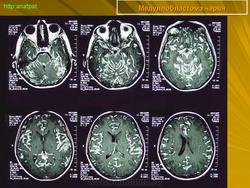

Медуллобластома - это опухоль, которая возникает из примитивных и эмбриональных клеток ЦНС. Локализируется исключительно в мозжечке и представляет 15-20% от детских опухолей мозга. 20% медуллобластом появляется в зрелом возрасте.

Это быстро растущая опухоль, очень злокачественна, имеющая тенденцию распространяться вдоль путей движения ликвора.

Вследствие локализации в мозжечке, обструкция путей циркуляции ликвора является достаточно частой и ранней, с последующей гидроцефалией. Синдром повышенного внутричерепного давления наряду с расстройствами равновесия, являются наиболее частыми и ранними признаками и симптомами.